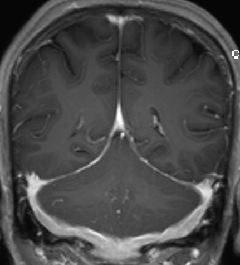

2015-4-1 MRI

2015-4-1